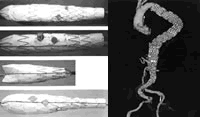

图1 4例患者接受定制的Zenith开窗和分支型支架移植物置入

图2 患者2随访CT血管造影显示,动脉瘤被隔离,而且腹腔干、肠系膜上动脉和双侧肾动脉通畅, http://www.100md.com